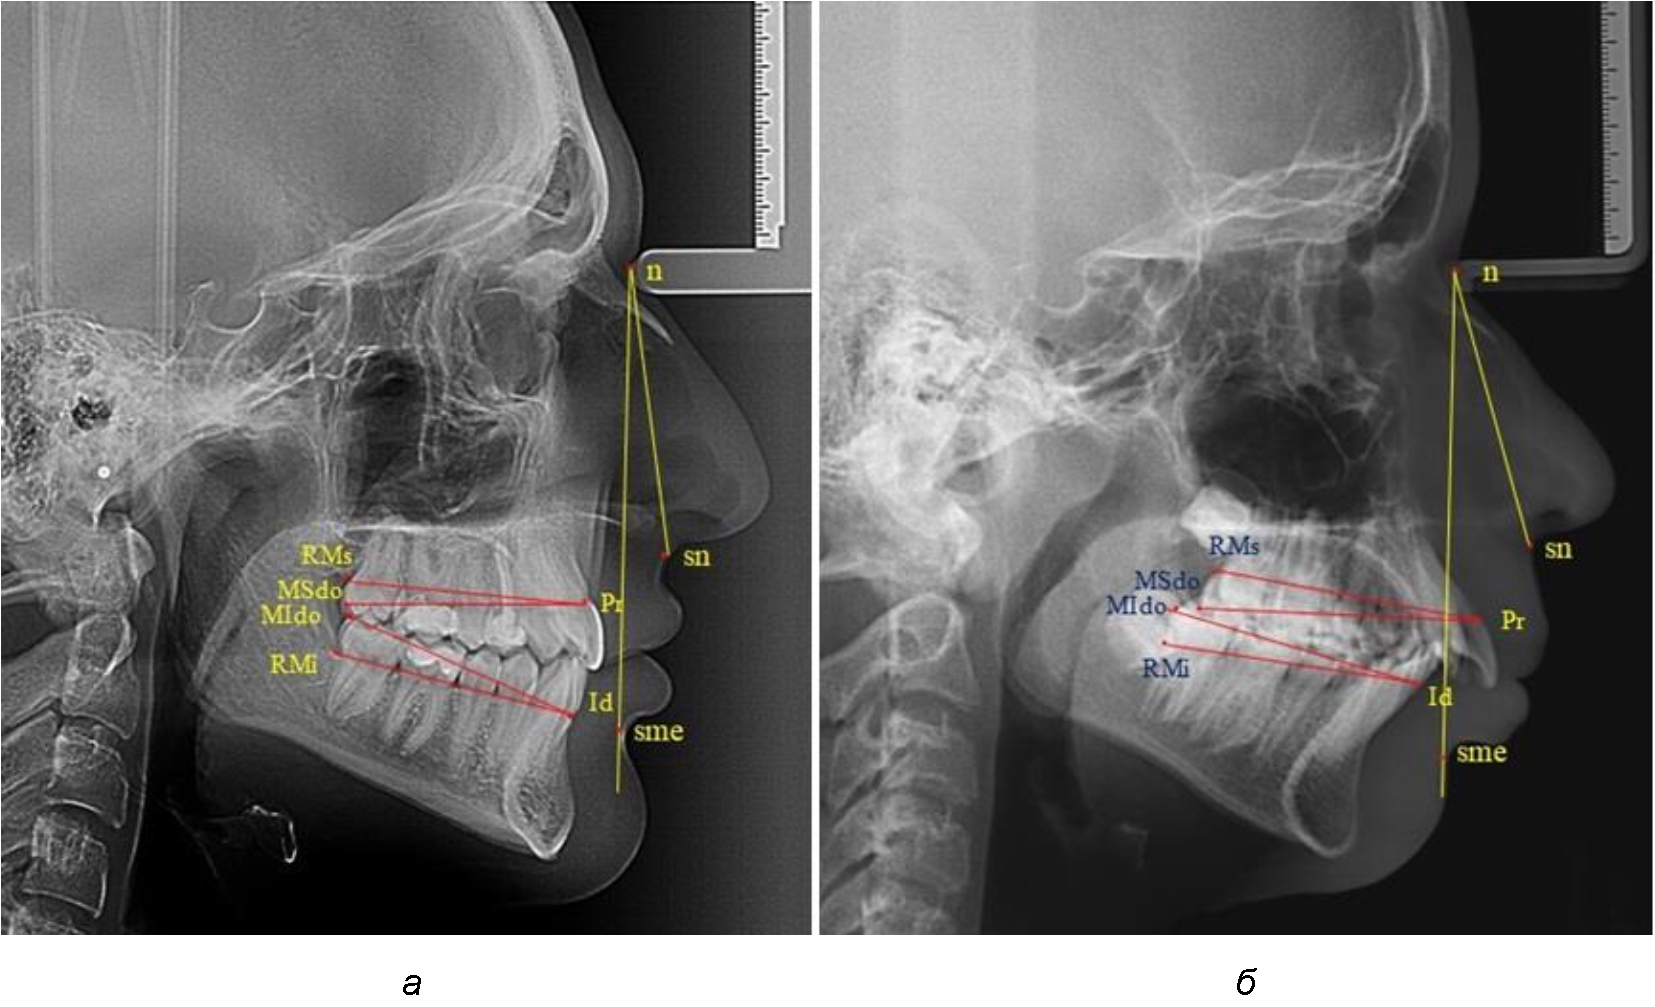

Измеряли межальвеолярное расстояние на верхней челюсти (Pr-RMs) и на нижней челюсти (Id-RMs) и сравнивали показатели между собой. Альвеолярно-окклюзионный размер на верхней челюсти (Pr-MSdo) сравнивали с аналогичным параметром нижней челюсти (Id-MIdo). При анализе 32 телерентгенограмм с дистальной окклюзией использовали те же ориентиры (рис. 1).

Рис. 1. Точки и линии телерентгенграмм при физиологической (а) и дистальной (б) окклюзии

При физиологических вариантах прикуса дистальные окклюзионные точки моляров, как правило, располагались практически рядом, в то время как при дистальном соотношении нижние моляры анализируемый окклюзионные точки, как правило, располагались позади верхних.

При сравнительном анализе носовой части угол составлял 28°, для которого соразмерность с гнатической частью составляла 17,3° (28/1,618 = 17,3°), в то время как в анализируемом случае угол значительно превышал расчетную величину и был 26°. Назально-супраментальный угол составлял 20°, что характерно для гнатической формы дистальной окклюзии. При анализе размеров верхней челюсти размеры ее межальвеолярного и альвеолярно-окклюзионного расстояний были на 4–5 мм меньше размеров нижней челюсти. В данном случае укорочение размеров верхней челюсти и увеличение тела, подбородка и угла нижней челюсти предполагало комплексную (ортодонтическую и хирургическую) реабилитацию пациента (рис. 2).